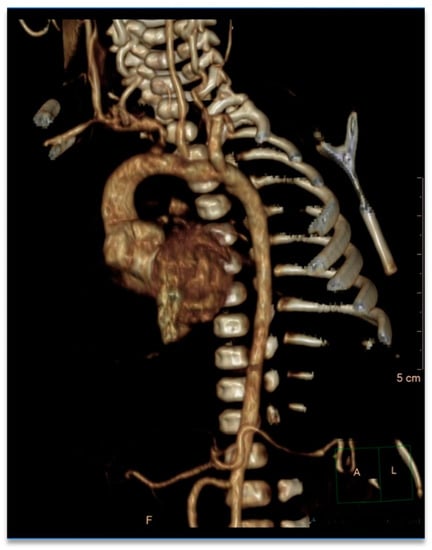

Cleft Palate and Aortic Dilatation as Clues for Loeys–Dietz Syndrome

2. Case Report